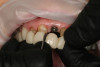

Fig 10. Finishing the semi-permanent self-cure composite long-term provisional while preparing for osseointegration of implant No. 9.

Figure 10

Fig 11. Semi-permanent self-cure composite provisionals Nos. 3 through 12 and 23 through 26 to establish function and esthetics and allow osseointegration of implant No. 9.

Figure 11